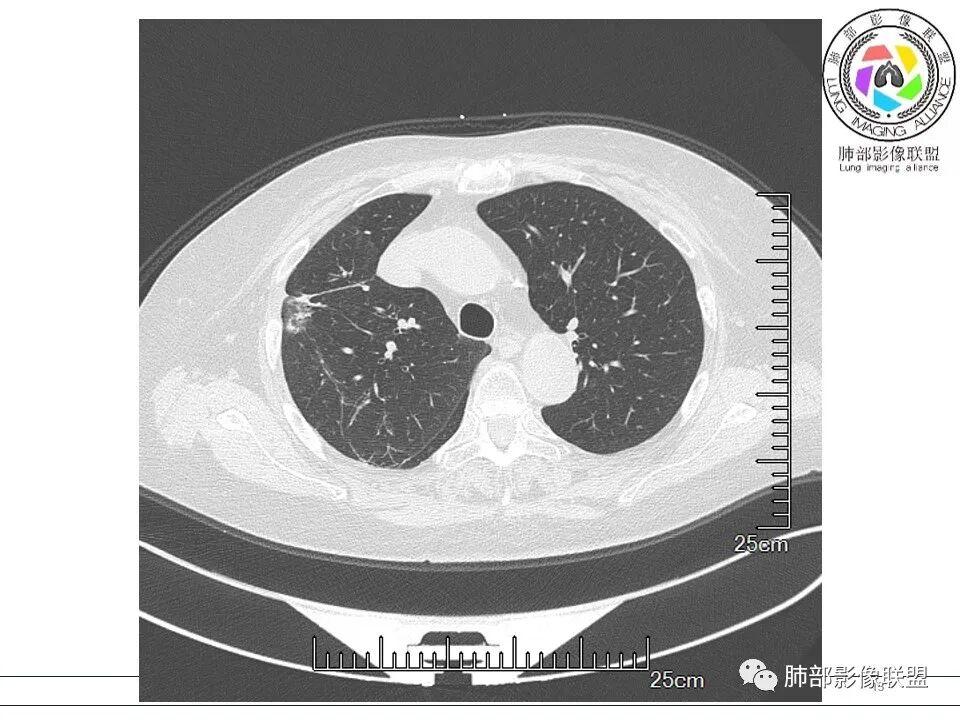

放射小白: 晨读病例:女性,70岁,风湿性多肌痛病史,右肺见不规则结节,边缘及周围见纤维索条影,考虑OP,药物性肺损伤。

小兜: 晨读,女,70岁,风湿性多肌痛病史一年,半月前体检发现肺部阴影,无症状,口服药物治疗。现片示:右肺胸膜下条形实变影,局部层面似见多结节融合,周边伴条索影。下方近叶间胸膜处斑片状实变影伴条索影,宽基底与胸膜相连。综合考虑为炎性病变,隐球菌或OP可能

宇宙: 右肺上叶胸膜下结节,多结节融合,长轴平行胸膜,边缘模糊,周围长索条,胸膜牵拉,近端支气管充气扩张,考虑隐球菌,鉴别OP

衡妈: 老年女性,右肺上叶沿胸膜下不规则实性病灶,长轴平行于胸膜,有结节融合感,边缘部分彭隆部分平直,周围可见数条纤维灶影,病灶内可见充气支气管征未达远端,首诊考虑慢性炎性肉芽肿,隐球菌?机化性肺炎?建议增强扫描及ct下穿刺活检。

晨读:女,70,未诉症状。风湿性多肌痛病史,口服强的松等药物治疗。胸部CT:右肺上叶多发不规则斑片影,沿支气管分布,部分病灶侧向融合、平行于胸膜,边缘平直内收为主、部分彭隆,周围模糊晕、可见数条纤维灶影,胸膜牵拉,病灶内可见充气支气管征、管腔不畅,考虑慢性炎症,PC?OP?鉴别腺Ca、SCLC等。

南边: 这个病例大方向没问题,炎性。目前大家都是考虑:隐球菌病、OP,其实这两个结论有重叠,而且这个病例很值得讨论,可惜,估计没有证实。影像特点:病灶长轴与胸膜平行,侧向融合特点明显,符合隐球菌病,问题是目前的状态,边缘收缩明显

内部支气管扩张,周围少量GGO,而且病灶离开了胸膜,附近长索条影,支持机化的改变